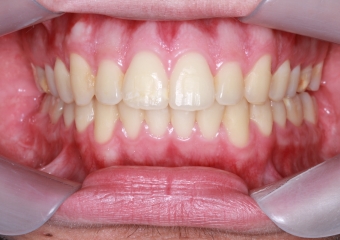

Mordida após cirurgia realizada em 2015 - Clínica Cliniface

Mordida após cirurgia realizada em 2015